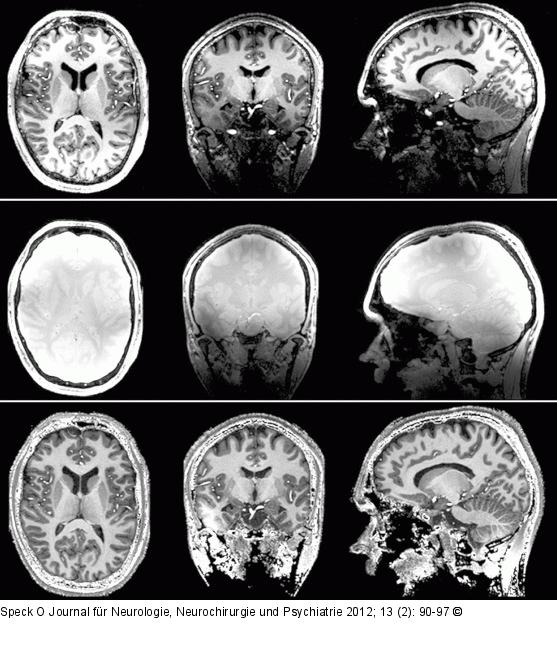

Abbildung 2: MPRAGE Dreidimensionale T1-gewichtete Aufnahme mittels „Magnetization Prepared Rapid Acquisition with Gradient Echoes“ (MPRAGE, wie alle folgenden Abbildungen aufgenommen mit einer 24-Kanal-Kopfspule [Nove Medical]). Durch die hohe Magnetisierung kann eine sehr hohe räumliche Auflösung von 0,6 mm isotrop in 15 Min. erreicht werden. Die nativen Daten (oben, in 3 Orientierungen reformatiert) zeigen jedoch starke Variationen in Signal und T1-Kontrast. Mittels einer Referenzmessung ohne Inversionspuls und kürzerer Wiederholzeit (Mitte) kann durch Division ein homogener kontrast- und detailreicher Datensatz generiert werden (unten). Lediglich im Temporallappen sind Bereiche erkennbar, in welchen die Inversion der Magnetisierung aufgrund zu geringer Kippwinkel nicht vollständig war. |

Dreidimensionale T1-gewichtete Aufnahme mittels „Magnetization Prepared Rapid Acquisition with Gradient Echoes“ (MPRAGE, wie alle folgenden Abbildungen aufgenommen mit einer 24-Kanal-Kopfspule [Nove Medical]). Durch die hohe Magnetisierung kann eine sehr hohe räumliche Auflösung von 0,6 mm isotrop in 15 Min. erreicht werden. Die nativen Daten (oben, in 3 Orientierungen reformatiert) zeigen jedoch starke Variationen in Signal und T1-Kontrast. Mittels einer Referenzmessung ohne Inversionspuls und kürzerer Wiederholzeit (Mitte) kann durch Division ein homogener kontrast- und detailreicher Datensatz generiert werden (unten). Lediglich im Temporallappen sind Bereiche erkennbar, in welchen die Inversion der Magnetisierung aufgrund zu geringer Kippwinkel nicht vollständig war. |